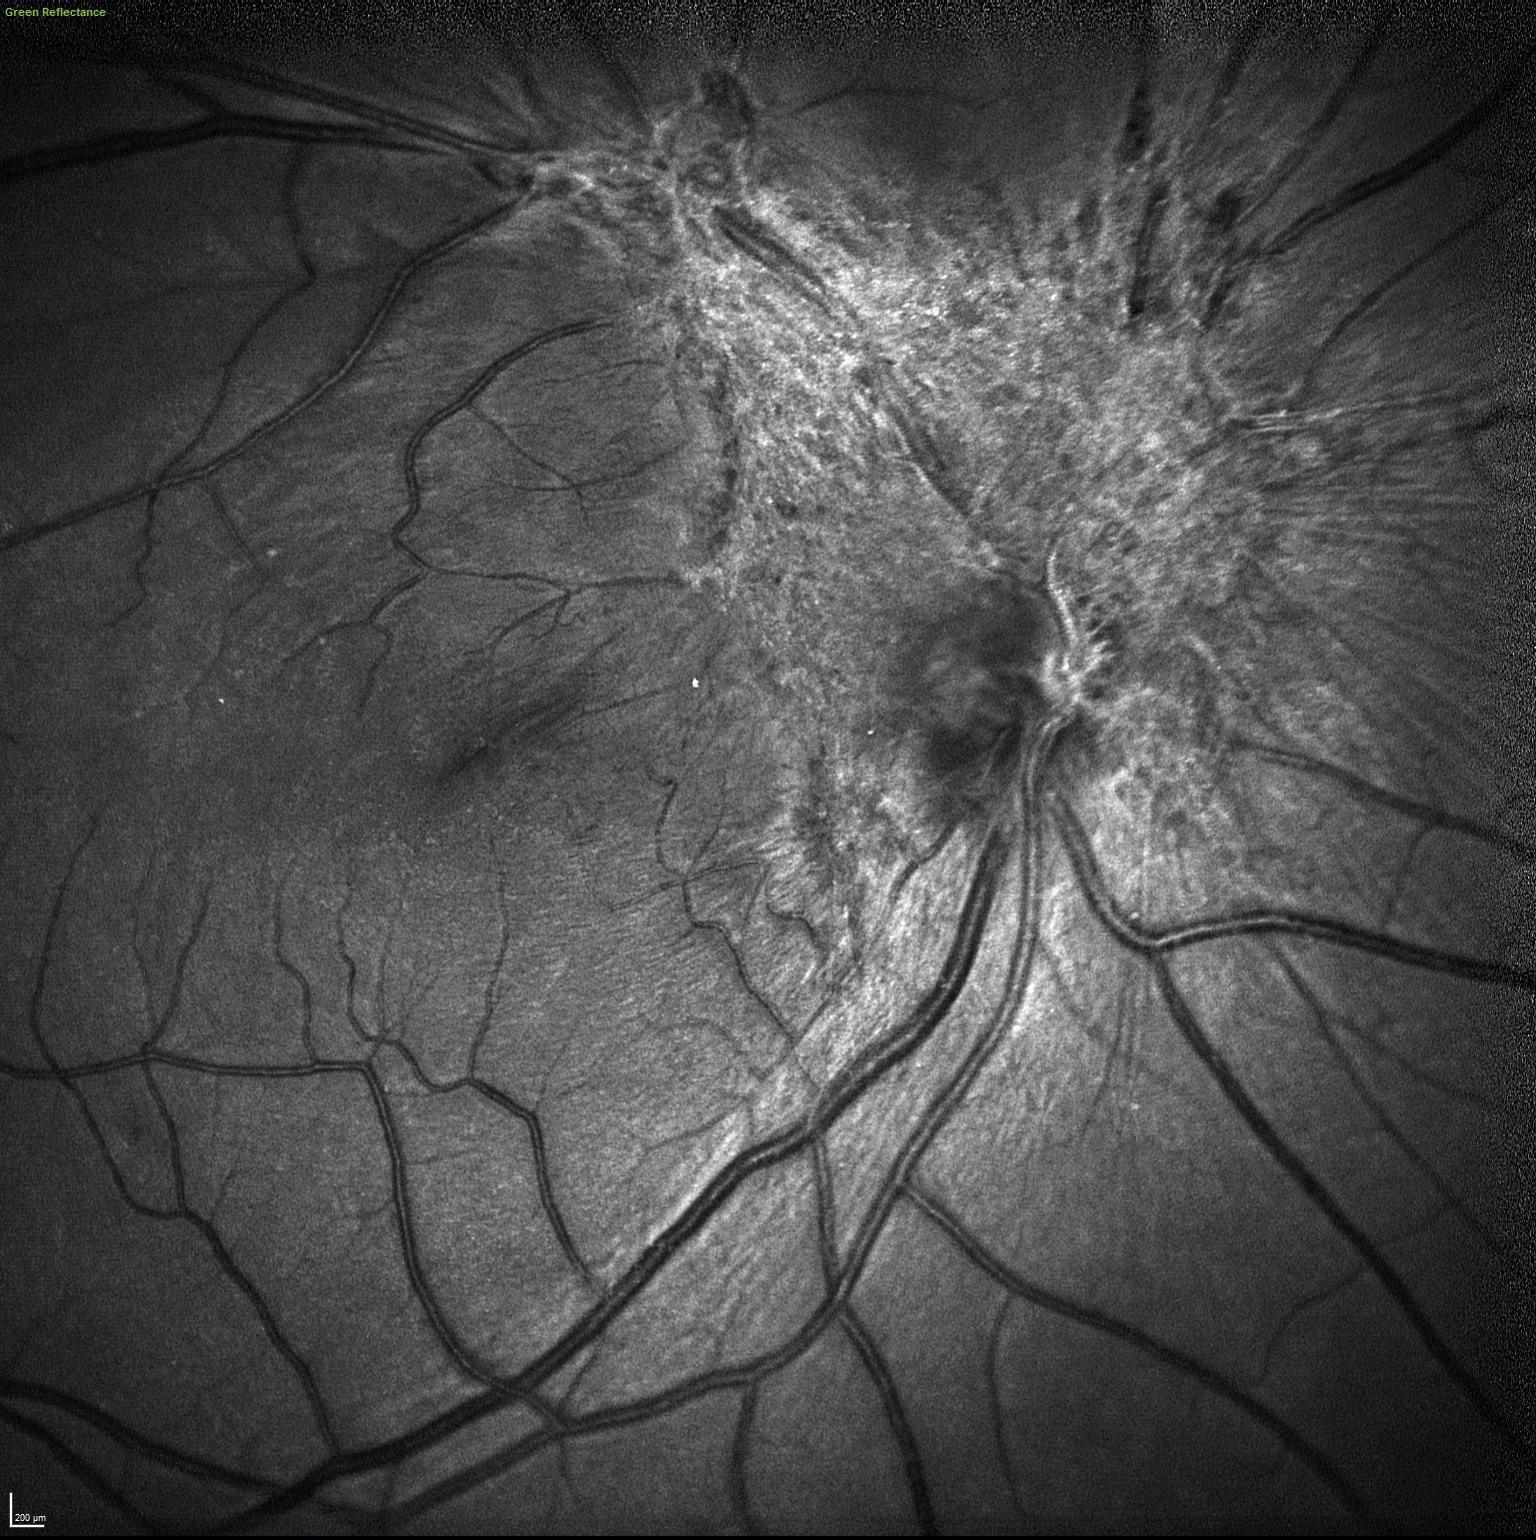

Reflectancia